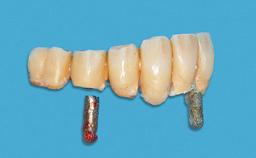

# of Implants 2

Type of Implants One-Piece

Attachment One-Piece

Defining Characteristics Fully edentulous lower jaw to be rehabilitated with two or more implants

Modality 2 interforaminal implants

SAC Level Advanced

Defining Characteristics Fully edentulous lower jaw to be rehabilitated with an implant-borne removable overdenture